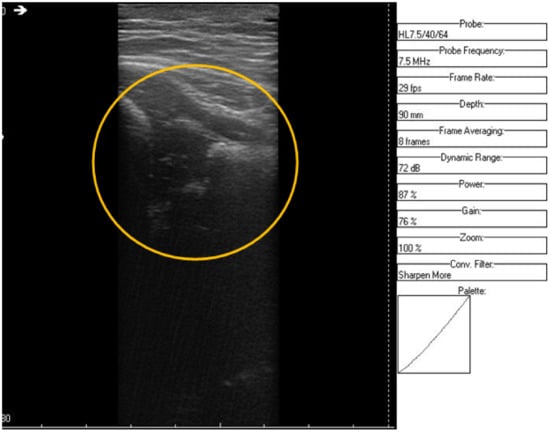

The original recording is displayed in Figure 3. As a first processing step, a color palette has been added to the original ultrasound in order to better highlight the noise and noise-free zones (Figure 4). The wavelet-based filter, as described in Section 2, is applied, and the processed image is shown in Figure 5.

We can remark, when analyzing the zoomed parts of Figure 4 and Figure 5 (the acetabulum), that in the original image speckle noise appears, strongly affecting the image. The filtering system proposed in this paper does not completely remove the speckle but brightens the image, at the same time not oversmoothing the original image. The main bone structure can be better outlined. A comparison between the same zoomed region of interest in the original image and denoising result, showing the disappearance of the speckle grains (Figure 6)—resulting thus in a smoother image where anatomical features can be better outlined.

Figure 5. Same region of interest as in Figure 4 was encircled in yellow. The interior speckle grains have disappeared.

Jpm 12 01328 g005